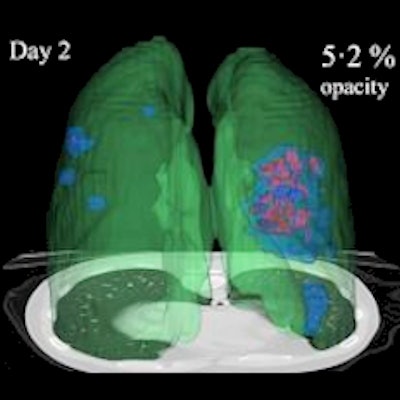

After verifying the AI lung segmentation results, radiologists then manually segmented the lung opacities and noted the opacity subtypes. Next, the researchers employed generalized temporal curves to correlate the CT data with lab measurements such as blood cell count and procalcitonin levels. 3D visualizations were also used to reconstruct the evolution of COVID opacities.

3D image visualizations show the evolution of COVID opacities over the course of the disease. Images courtesy of Nvidia.

3D image visualizations show the evolution of COVID opacities over the course of the disease. Images courtesy of Nvidia.The researchers found that lung opacities appeared in an average of 3.4 ± 2.2 days prior to symptom onset and peaked an average of 0.6 ± 3.1 days after symptoms began. Ground-glass opacity onset was earlier, and it resolved later than consolidation, according to the authors. As for lab results, lactate dehydrogenase and C-reactive protein peaked earlier than procalcitonin and leukopenia.